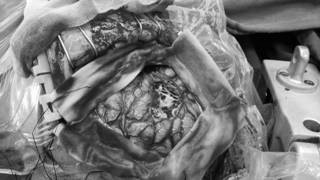

微侵袭神经外科的吴杰主任考虑小月的癫痫灶为右额中央区的结节性硬化病变。几日后,吴杰主任为其实施了“右额中央区癫痫灶切除术”,术中经导航确认病灶组织;皮层电极检查局部有少量尖波发放,电刺激术区均未有运动反应,医生在显微镜下切除病变。

全切后